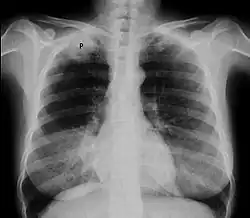

![]() Zdjęcie przeglądowe klatki piersiowej, obraz typowy dla guza Pancoasta | |

Guz Pancoasta (zespół Pancoasta, ang. Pancoast syndrome) – szczególna postać kliniczna raka oskrzela, zlokalizowanego obwodowo w okolicy szczytu płuca mogący naciekać żebra, kręgi, ścianę klatki piersiowej i struktury otworu górnego klatki piersiowej. Guz Pancoasta musi naciekać opłucną ścienną i wywoływać objawy neurologiczne, sama lokalizacja w szczycie płuca nie wystarcza do klasyfikacji nowotworu płuc jako guza Pancoasta[1]. Często dochodzi do uszkodzenia splotu ramiennego i zwoju gwiaździstego[1]. Stanowi około 5% przypadków raka płuc[2].

Około 70% guzów stanowi gruczolakorak, resztę stanowi rak drobnokomórkowy i olbrzymiokomórkowy[2]. Pierwszym objawem bywa stały ból okolicy barku, łopatki, a czasami także ramienia spowodowany uciskiem lub naciekaniem splotu ramiennego, opłucnej ściennej, żeber I-III; jest to ból charakterystyczny dla tej choroby[3]. Charakterystyczny jest zespół objawów neurologicznych spowodowanych uciskiem splotu barkowego oraz zespół Hornera (m.in. ptoza, mioza, enoftalmia) spowodowany uciskiem lub naciekaniem zwojów współczulnych. Guz Pancoasta z definicji jest zaawansowanym nowotworem (guzy T3 i T4 w klasyfikacji TNM)[2].